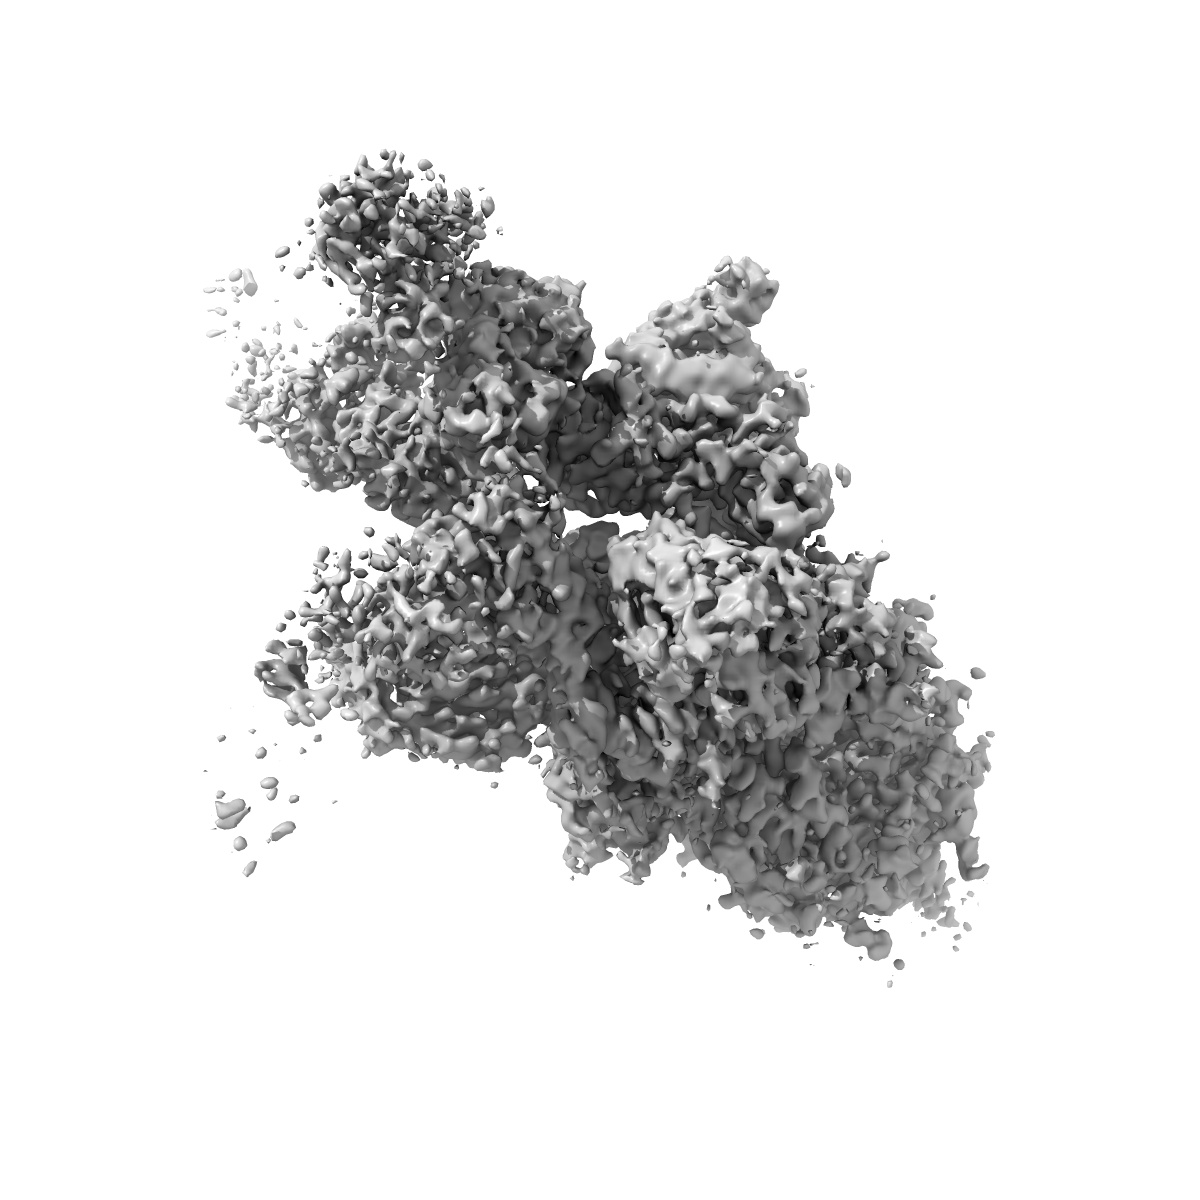

EMD-34130

Omicron BA.4/5 SARS-CoV-2 S in complex with TH272 Fab

Single-particle3.2 Å

Sample: Omicron BA.4/5 SARS-CoV-2 S in complex with TH027 Fab

Fitted models: 7yvk